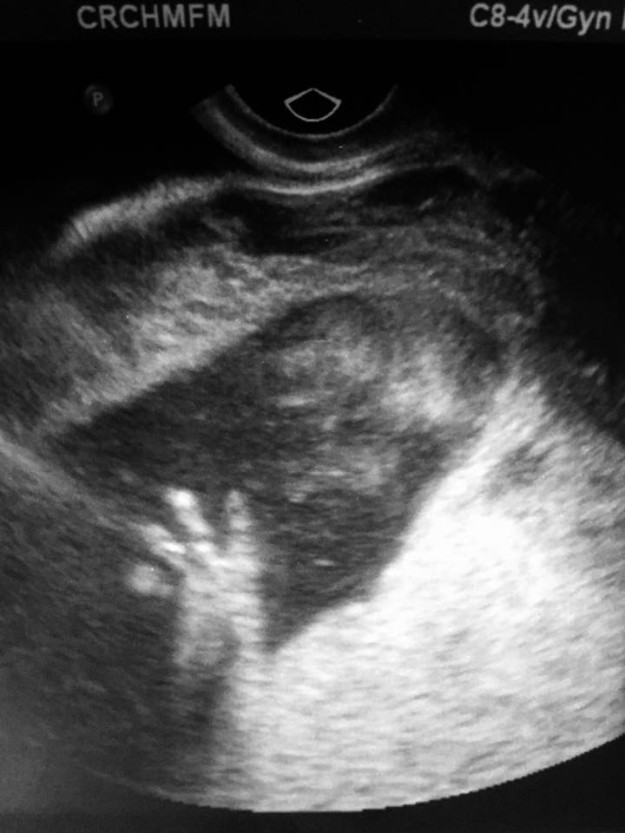

Cuando Lindsay estaba en la semana 18 de gestación, durante un estudio de rutina, los médicos descubrieron algo inusual. ¡En el cuello del bebé no nato crecía rápidamente la inflamación!

Al principio, los médicos se mostraban optimistas, y esperaban que la enfermedad se detuviera por sí sola, para ayudarlo después del nacimiento. ¡Sin embargo, dos semanas después, el tumor se duplicó!